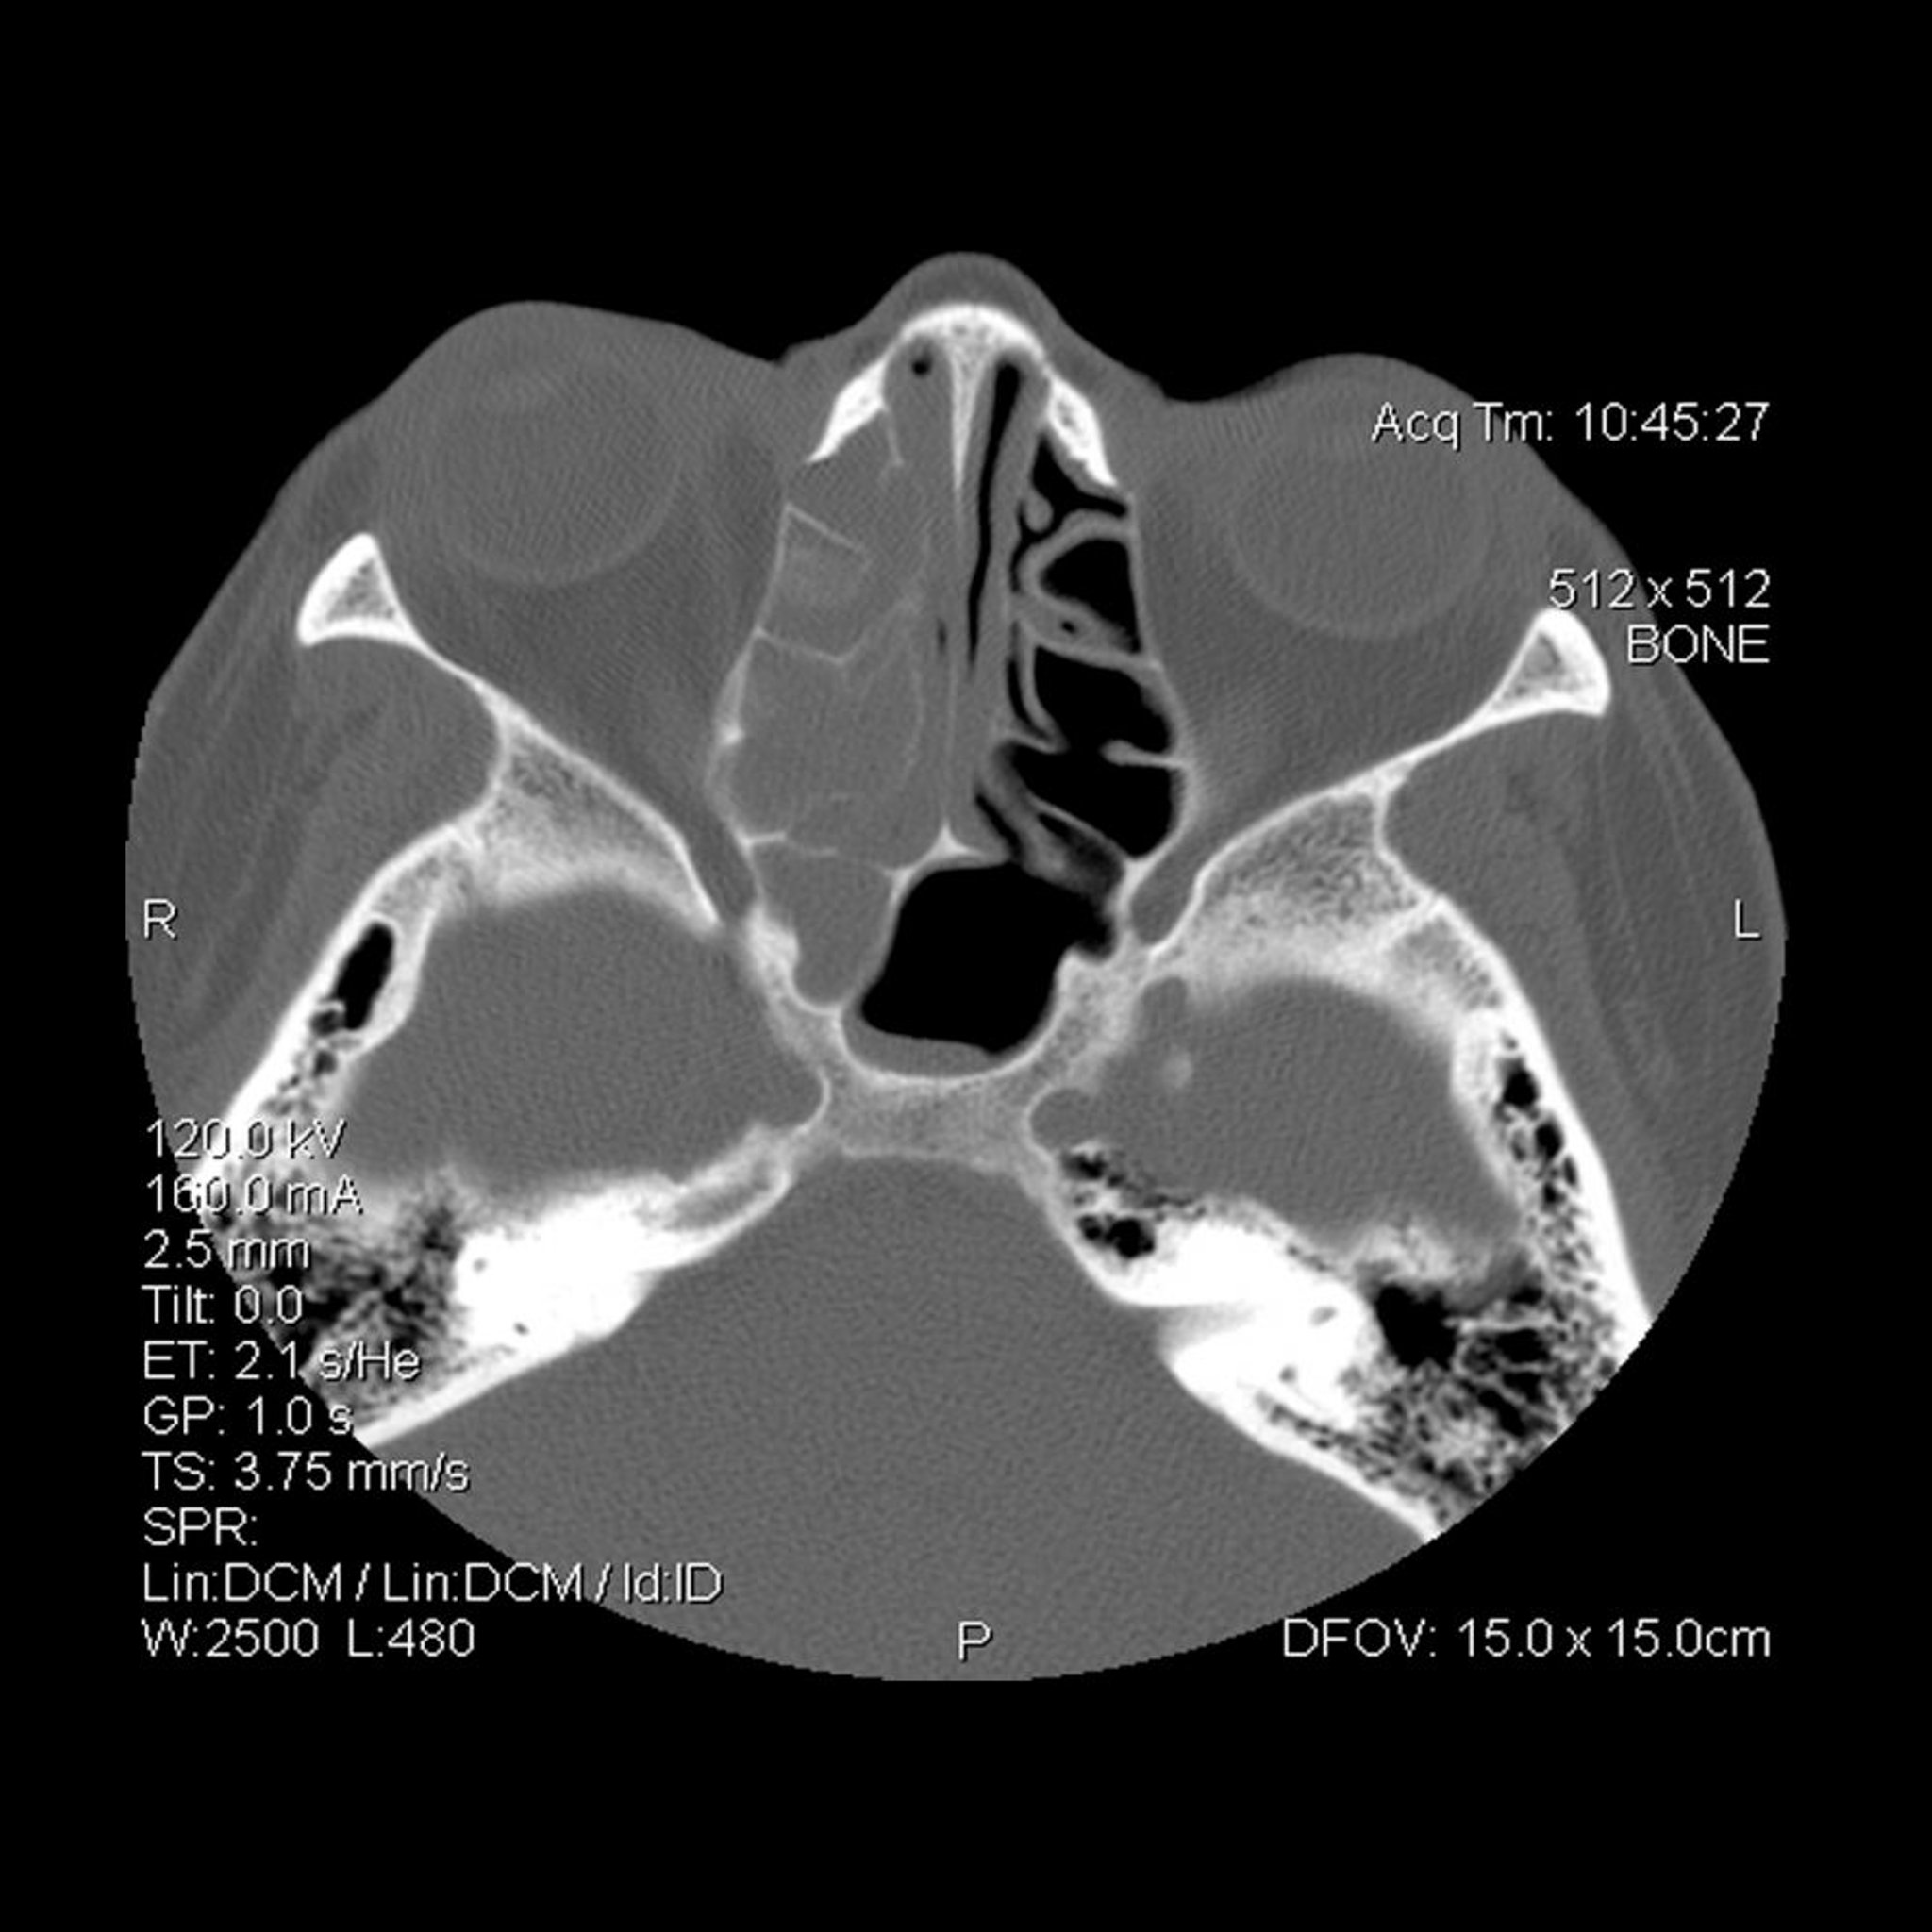

Opacification des sinus ethmoïdaux et sphénoïdaux droits (à gauche de l'observateur).